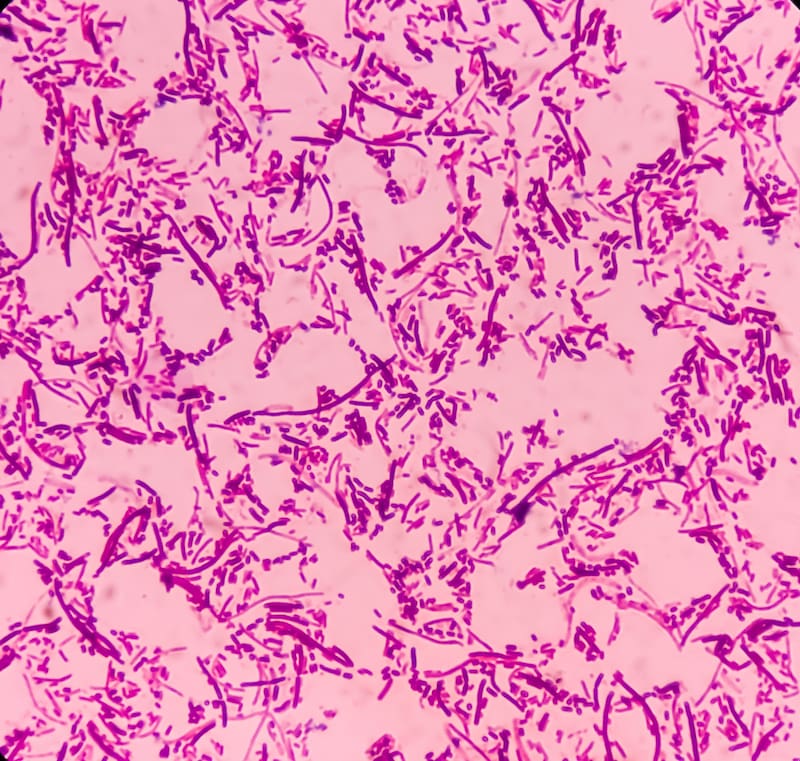

¿Qué es la Salmonella?

La Salmonella es un género de bacterias que pueden causar infecciones en el tracto gastrointestinal y otras partes del cuerpo. Las bacterias son patógenos comunes responsables de enfermedades transmitidas por alimentos, como carnes crudas o mal cocidas, huevos crudos, productos lácteos no pasteurizados y frutas o verduras contaminadas.